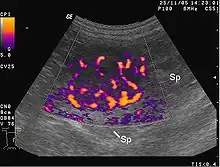

Image écho-Doppler montrant l'hypervascularisation

L’angiogenèse tumorale est la prolifération d'un réseau des vaisseaux sanguins qui pénètrent dans les croissances cancéreuses, fournissant des substances nutritives et de l'oxygène et enlevant les déchets : le chercheur Judah Folkman montre en 1971 que la tumeur ne peut grossir sans angiogenèse au-delà de mm3[6]. La tumeur angiogénétique commence en réalité lorsque des cellules de tumeur cancéreuses laissent échapper des molécules qui envoient des signaux au tissu hôte normal qui l’entoure. Cette signalisation active certains gènes dans le tissu hôte, lequel, à son tour, permet aux protéines de susciter la croissance de nouveaux vaisseaux sanguins.